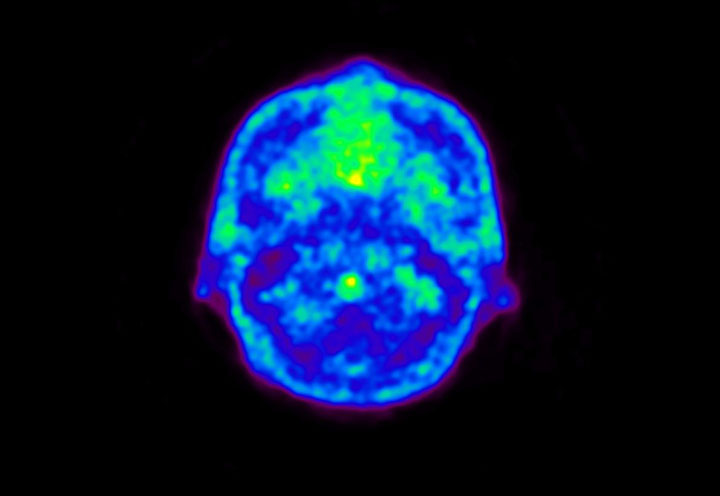

Head / Case5 : Amyloid

Sagittal

Courtesy : Kindai University Hospital

- Imaging protocol

- Injected dose: 4.27 MBq/kg, 18F-Flutemetamol

- Uptake time: 99 minutes

- Scan time: 20 minutes